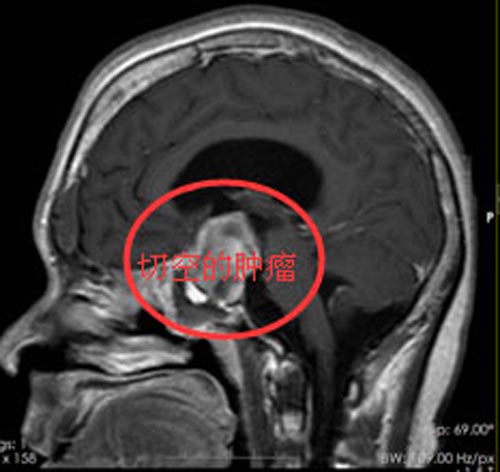

发现是鞍区肿瘤后,经患者及家属同意,鲁明副院长主刀行“内镜经鼻蝶鞍区占位切除术”,顺利全切除了肿瘤。术后病理证实为“生长激素型垂体瘤”。